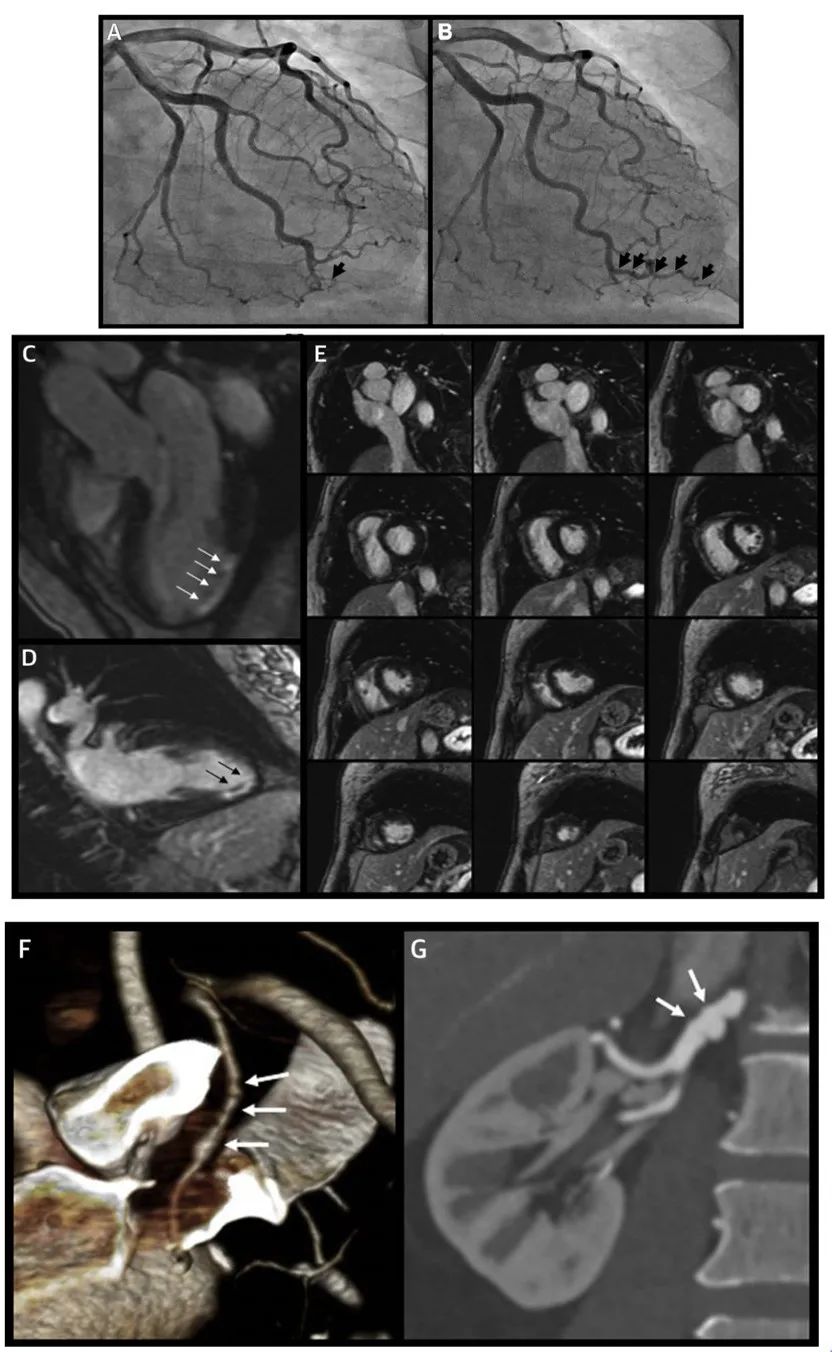

下面给大家举个例子(图3),该患者临床表现为急性心肌梗死,但初次造影提示正常,后行心脏核磁发现下侧壁延迟强化提示该部位梗死,重新读片考虑有一远端钝缘支闭塞,复查造影发现该血管已恢复显影。同时该患者发现左内乳动脉和右肾动脉存在FMD。

图注:A第一次造影,B第二次造影,C-E心脏核磁,F内乳动脉,G右肾动脉